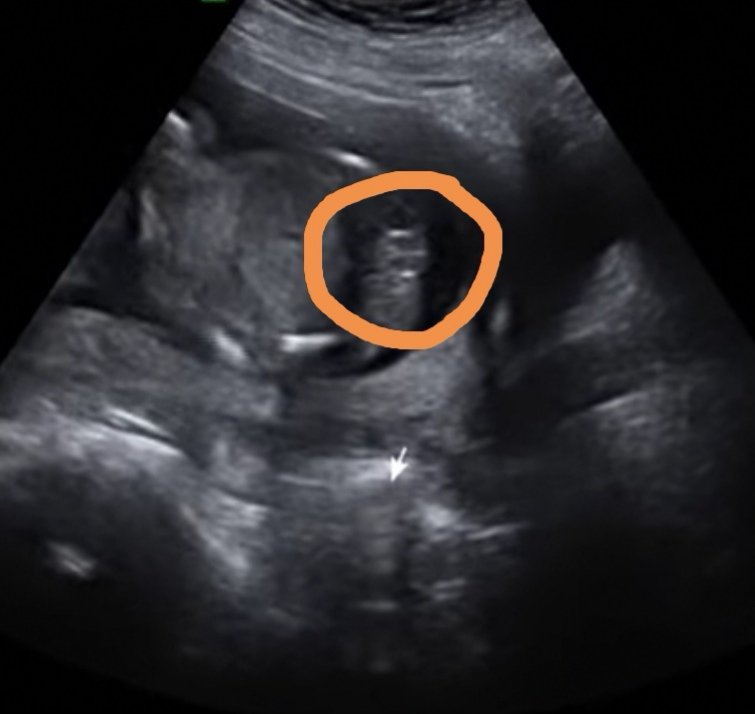

Dziewczyny mała zagadka. Jaka to płeć?